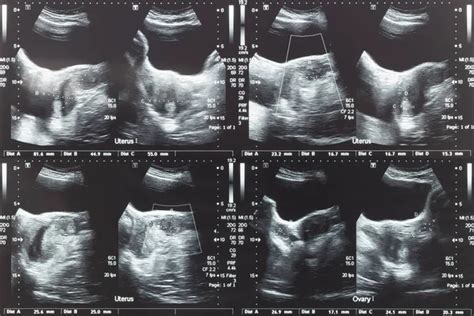

A nő vizsgálatával kiderítjük, hogy milyen erősek a petefészkei, és felmérjük a petesejtek minőségét. A vizsgálat részeként a nő ultrahangos kismedencei vizsgálaton, hormonszint-vizsgálaton, illetve genetikai és immunológiai vizsgálaton vesz részt, ahol elemzik reprodukciós képességét. Ha a nő petesejtjeit gond nélkül fel lehet használni a kezeléshez, akkor azokat rövid ideig tartó általános érzéstelenítésben a petefészekből történő szúrással és leszívással nyerik ki. Ha olyan probléma merül fel, amely nem teszi lehetővé a saját petesejtek használatát a sikeres kezeléshez, akkor adományozott petesejtek használatát javasoljuk. Ebben az esetben széles körű adatbázisunkból kiválasztható a megfelelő donor, a kezelés pedig késedelem nélkül folytatódhat.